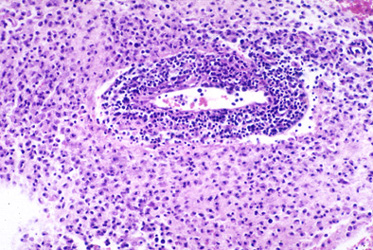

Question 25: A 42 year old woman had right-sided weakness progressing to hemiparesis in 3 to 4 weeks. MRI shows an enhancing lesion in the left centrum semiovale adjacent to the corpus callosum. A stereotactic biopsy is obtained (shown below). The findings suggest:

Correct. The image shows a poorly-defined inflammatory lesion with two areas of perivascular small lymphocytes. The pathology, together with rapid onset of the neurological deficit and the location of the lesion, is most consistent with an inflammatory demyelinative disease, acute MS or ADEM.

Incorrect. The image shows a poorly-defined inflammatory lesion with two areas of perivascular small lymphocytes. The pathology, together with rapid onset of the neurological deficit and the location of the lesion, is most consistent with an inflammatory demyelinative disease, acute MS or ADEM.